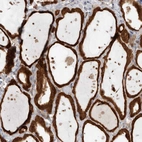

Immunohistochemical staining of human thyroid gland shows strong cytoplasmic positivity in glandular cells.